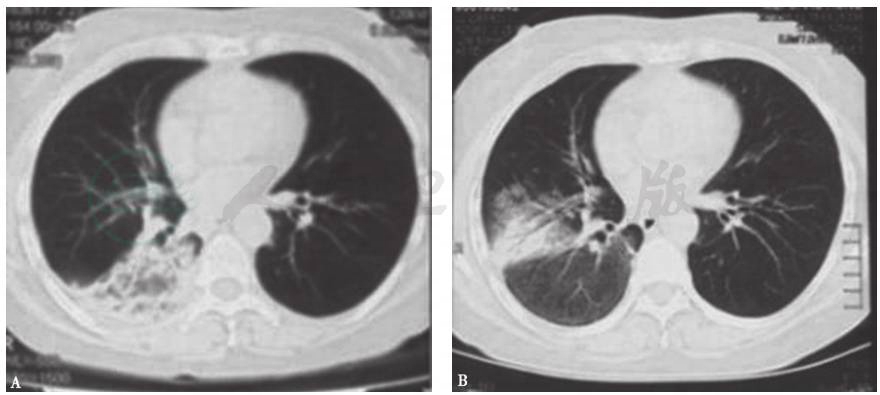

肺部真菌感染常继发于免疫功能低下和粒细胞缺乏状态等情况,常见病原体包括曲霉菌、肺孢子菌、隐球菌及念珠菌等。肺部曲霉菌感染典型的影像学表现为晕征和新月征(图4),亦可表现为反晕征(图5)。肺孢子菌肺炎的主要影像学表现为双肺弥漫间质性改变伴小叶间隔增厚。个别免疫功能正常者也可发生原发肺曲霉菌病和肺孢子菌肺炎。隐球菌对人类而言是机会致病菌,易侵犯中枢神经系统,引起脑膜炎,感染者多有鸽子等接触史。念珠菌所致肺感染的发生概率很低,诊断困难,多为导管相关性或抗菌药物所致二重感染,罕见原发感染。本例患者的临床过程和胸部影像学表现及演变与曲霉菌感染相近,虽无曲霉菌感染的高危因素,但仍需进一步检查相应指标以排除之。

图4 侵袭性肺曲霉菌病胸部CT表现

女性患者,35岁,乏力1个月,发热5天,诊断为粒细胞缺乏症合并侵袭性肺曲霉菌病。胸部CT可见双肺多发实变斑片影,多发晕征结节伴新月形空洞形成

图5 肺曲霉菌感染胸部CT表现

女性患者,55岁,间断发热1个月,咳嗽1周,痰中带血1天,诊断为侵袭性肺曲霉菌病。胸部CT可见双肺多发结节影伴反晕征形成